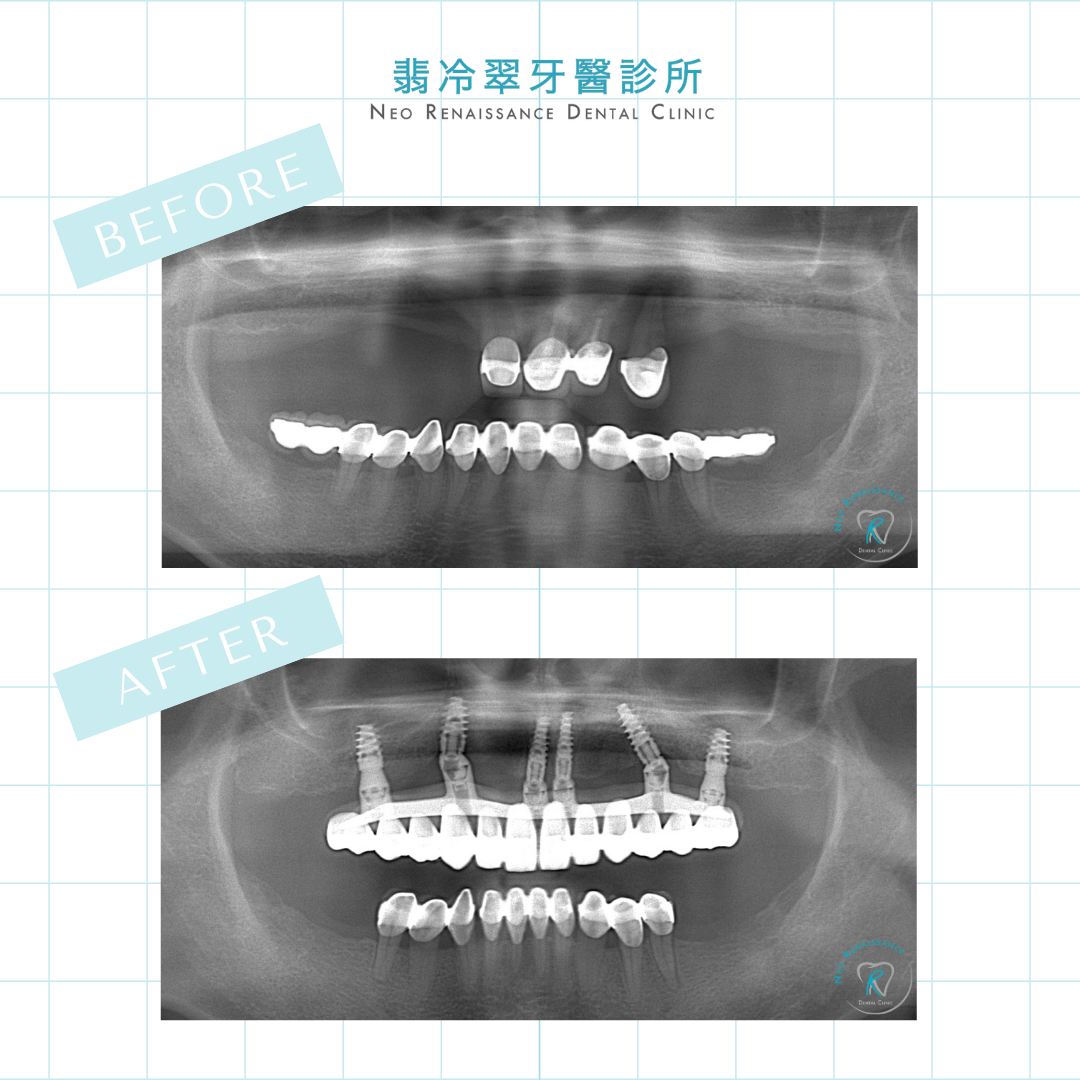

All-on-4的原理是在舒眠麻醉下,將壞牙全部拔除,接著植入至少4根人工牙根,麻醉醒來後再裝上全口臨時假牙,病人就可以帶著新牙回家吃晚餐。一舉解決多年缺牙、活動假牙難以咀嚼的困擾!等待數個月牙床骨完全癒合後,再更換成正式假牙。由於

All-on-4的人工牙根設計植在骨質量最多的地方,並以斜張橋原理增加受力面積、共同支撐假牙,也因此能只靠4~6顆人工牙根撐起全口假牙!可以有近乎真牙的咬力、費用也相對傳統全口